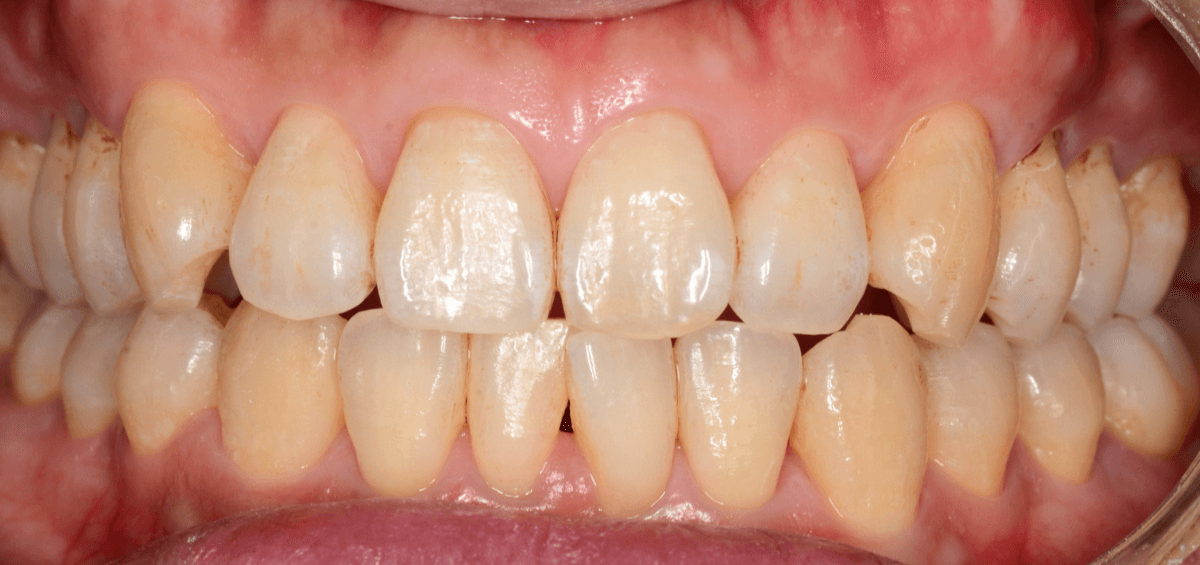

Case.1

こちらの患者さんも、「見た目を綺麗にしたい」というご希望で来院された患者さんです。

主な着色部位と歯石はこちらです。

こちらの方は、着色の割には歯石は少量が表面上にとどまっている状態でしたので、時間をお取りしてしっかり歯周辺をクリーニングする「ビューティー・クリーニング:60分 1万円」をご提案し、選択されました。

60分かけて、歯をクリーニング・仕上げにコーティングをしました。